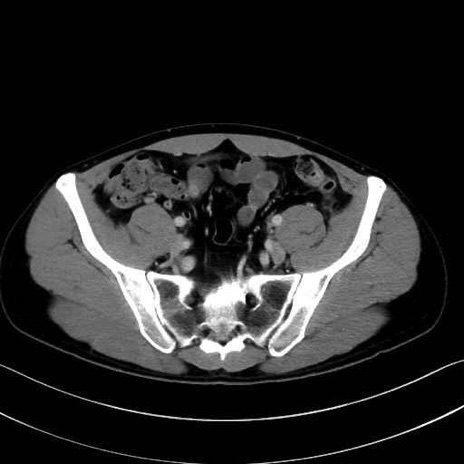

梨状筋(piriformis muscle) のCT画像の解剖

外閉鎖筋 (Obturator externus)

大腿方形筋 (Quadratus femoris)